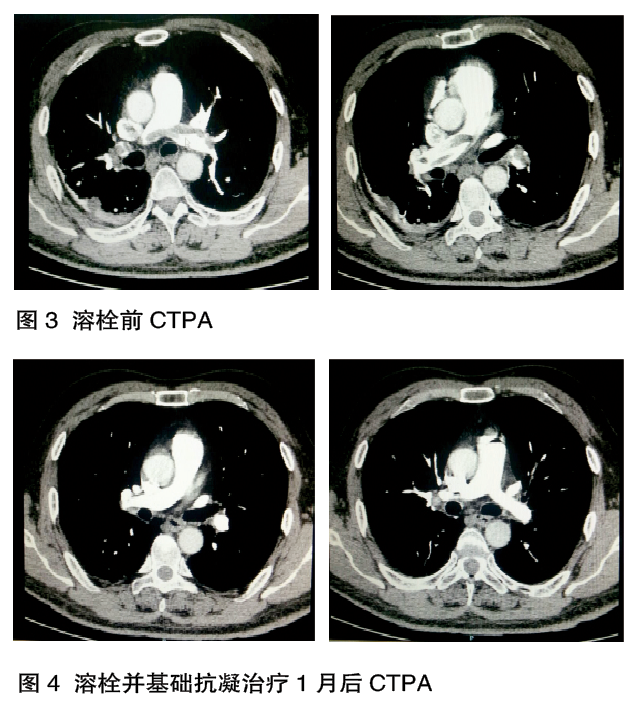

肺血管CT造影:双肺动脉及其分支多发栓塞,右肺下叶炎症,右侧胸腔积液(图3)。

阿替普酶50 mg 50 ml注射用水,2 h静脉输液。溶栓治疗后根据APTT结果,继续给予低分子肝素足量抗凝后加华法林2.5 ~3.75 mg,根据INR结果调整剂量抗凝治疗后复查相关检查。经1个月的抗凝治疗后症状明显好转,复查CTPA(图4),心脏彩超,均恢复正常。